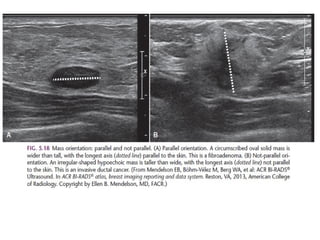

The shape of a mass is either round, oval or irregular.

Always make sure that a mass that is found on physical examination is

the same as the mass that is found with mammography or ultrasound.